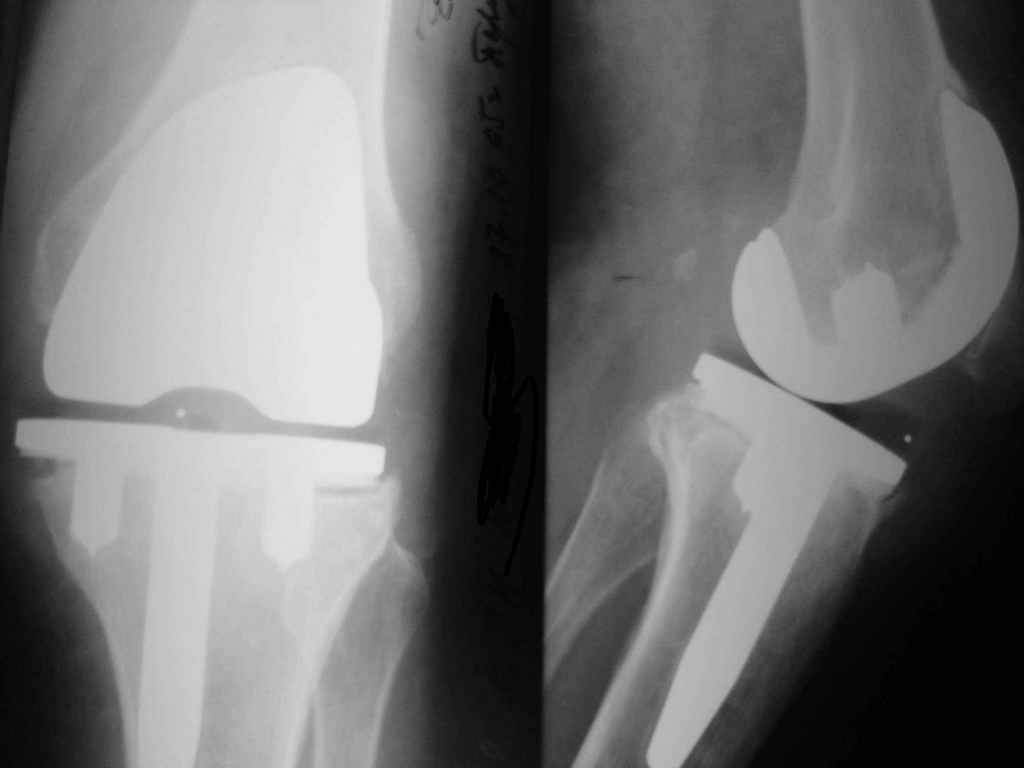

Уважаемые коллеги. Пациентка 65 лет соматически сохранна 6,5 месяцев назад выполнено замещениеколенного сустава интегральным эндопротезом Фримана Самуэльссона - цемент, по поводу ДОА. Послеоперационное течение с длительным субфебрилитетом. Местно без особенностей и выписана домой на 28 сутки с обьемом движений в колене 90 град. с частичной опорой. Дома отмечала субфебрильную лихорадку. Живет в небольшом поселке далеко от цивилизации. Контрольный осмотр в 3 месяца особых клинических проблем лечащий врач не нашел. Однако рентгенологически отмечены зоны остеопороза вокруг компонентов, на которые не обратил внимание. С 4 месяца отметила ухудшение - отек в колене, ограничение движений и боль. Лечилась у местного врача-хирурга (нестероиды и местно мазилки) - без эффекта. Обратилась только в 6,5 мес. Движения в суставе 20 град, отечность колена, выпот по УЗИ. Боль неопределенная, ходит с тростью. Лихорадки нет, в ан крови СОЭ 36 остальное норма, острофазовые тесты СРР повышен вдвое = 12 (при норме 6) Ревмотест - норма..Пункция - посев - роста не дает. Пробовали артроскопию - артрофиброз. Трудности осмотра из-законтрактуры и спаек. Рентгенограммы в динамике - в приложении (динамика с ухудшением). Вопросы:1. Инфекция? или остеопения местная? 2. Ревизия или подождать и полечить остеотропами? Благодарю заранее за любой совет. А Рыков. Хабаровск.

Показание к ревизии - нестабильность протеза (его компонентов) В приведённом Вами случае на Рг очевидная зона резорбции вокруг тибиального компонента следствие этого его нестабильность. Наиболее вероятна вялотекущая инфекция( судя по показателям крови и клиническим проявлениям: отек, боль, выпот и как следствие - ограничение функции)

Надеяться на чудо, что тибиальный компонент *самостабилизируется* едва ли приходится, наоборот, отсрочка ревизии усугубляет околопротезную деструкцию и ревизия технически усложняется за счет дефицита опорной кости, придётся изобретать с графтами и спейсерами, а это дополнительные расходы (в данном случае время - деньги :-))